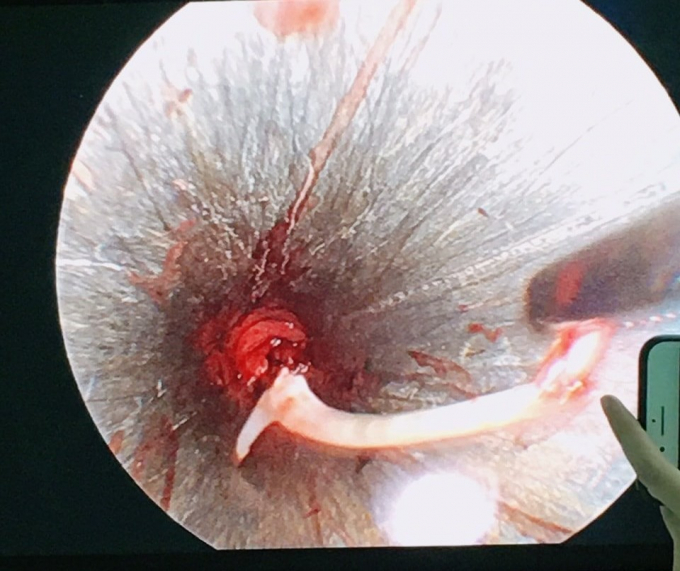

Bác sĩ dùng dụng cụ nội soi kéo chiếc xương cá ra ngoài cổ họng bệnh nhân. Ảnh: Pháp luật Việt Nam |

Ngay sau đó, bệnh nhân được điều trị kháng sinh, chống viêm để bớt phù nề. Đến ngày 13/12, bệnh nhân được chỉ định gây mê nội soi lấy dị vật.

Đến nay, sau 3 ngày dị vật được bác sỹ tìm thấy và lấy ra, bệnh nhân đã hồi phục sức khỏe, hết hẳn đau đớn.